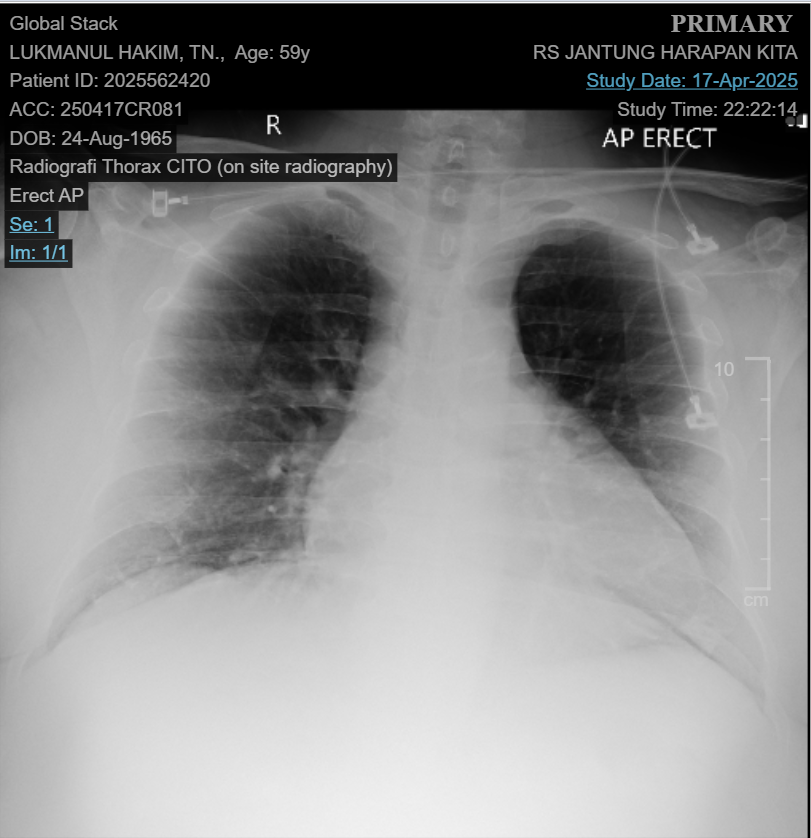

A 59 year-old male presented with angina pectoris during daily activities. The patient has a history of repeated rehospitalization 4 times within the last 5 months due to similar complaints, accompanied by a low pulse rate. Risk factors included hypertension , diabetes, obesity and dyslipidemia. Physical examination findings were within normal limits.

Relevant Test Results Prior to Catheterization